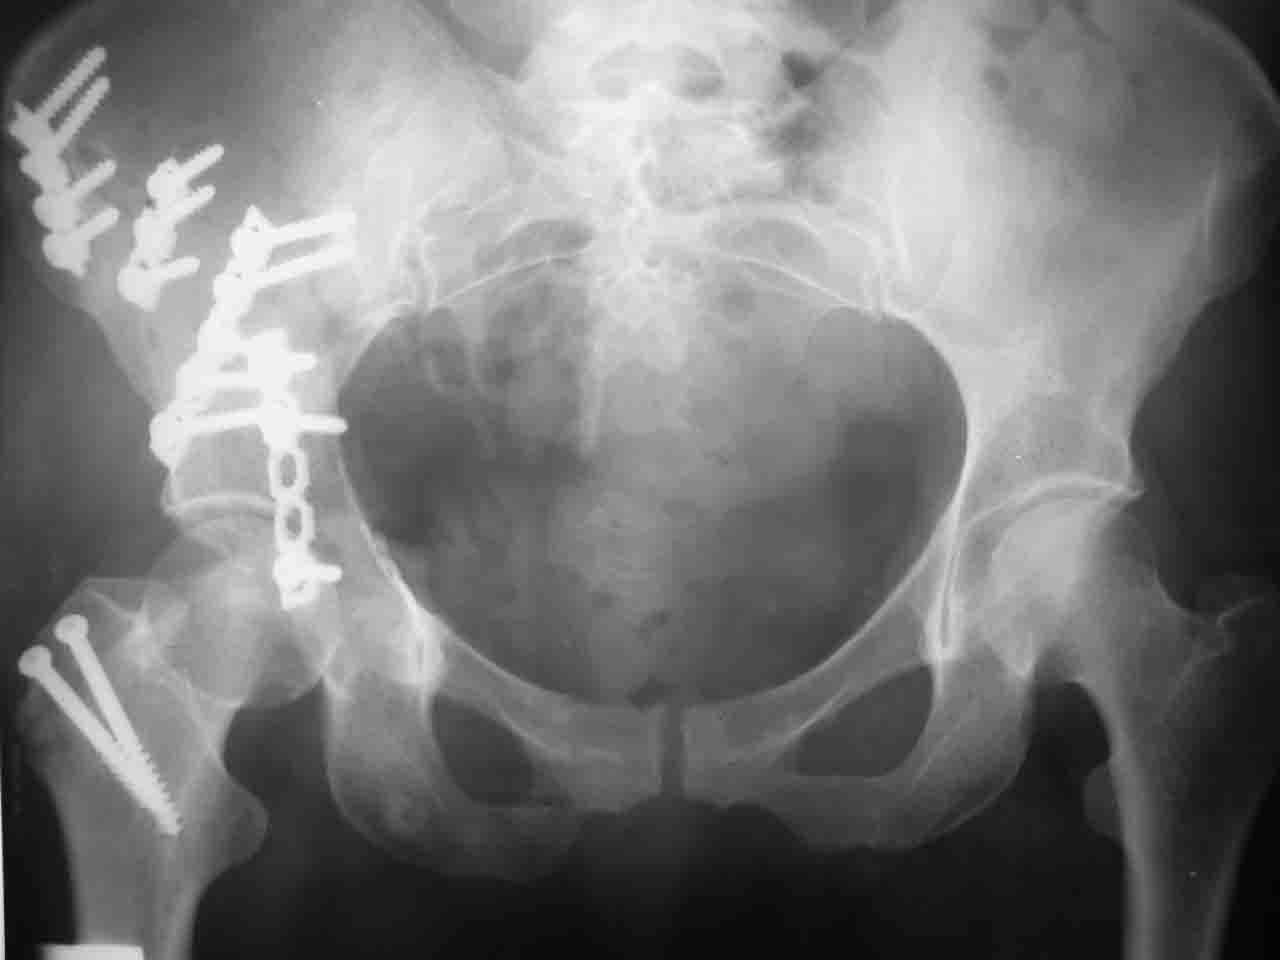

форуме и скелетном вытяжении. С репозицией и фиксацией задней колонны и отдельно задне-верхней стенки впадины проблем не возникло. Послеоп. Рг граммы в приложении. Если возникнут какие-либо дополнения или поправки - был бы признателен.

Спасибо за комментарии и рекомендации. Откровенно говоря, больного я прооперировал на прошлой неделе, через 5 дней после аварии и проблем с ним пока никаких нет, на удивление при достаточно обширной диссекции (илиофеморальный доступ) болей практически нет, так что больной самостоятельно садится в кровати, выполняет активные движения в оперированном суставе, сгибая до 60 градусов пока, далее с ассистенцией.

Причиной обращения к сообществу были возникшие непосредственно после операции сомнения и разочарования полученным качеством репозиции: а надо ли было трогать перелом вообще, репозиция передней колонны технически была очень сложна для меня, хотя реконструкции была в той же последовательности, что Д-р А.В.Рунков рекомендовал, в какой-то момент безуспешных манипуляций стал думать о *вторичной конгруэнтности*, которую не так давно обсуждали на

Вопрос доступа к вертлужной впадине при остеосинтезе задача не простая. Конечно, у Летурнеля и Тайла всё давно описано, нам остается только брать на вооружение. Но сами понимаете, что не бывает двух одинаковых ситуаций, поэтому в каждом случае вопрос решается сугубо индивидуально. Наша главная цель - восстановить анатомию с нанесением минимальной дополнительной травмы тазобедреннному суставу, думаю с этим никто не поспорит. Расширенный илиофеморальный доступ уж слишком травматичен (как сказал один коллега "таз лежит отдельно, больной отдельно").Стоит ли делать из пациента анатомический препарат для того чтобы легче ориентироваться. Да и нужно ли собирать всю "мозаику"? Мы применяли при таких операциях своеобразную операционную хитрость - сначала устраняли грубое смещение крыла под гребнем с фиксацией так называемой "плавающей" пластиной (временно фиксированной на двух винтах)- доступ или продлевали боковой, или делали небольшой дополнительный разрез над гребнем. Это позволяло устранить грубое смещение и захождение отломков тела повздошной кости, что значительно облегчало репозицию и остеосинтез впадины над сводом. Основное внимание конечно же уделяли нагружаемому задне-верхнему отделу. Сообщите ваш адрес, пришлю схемы и рентгенограммы.